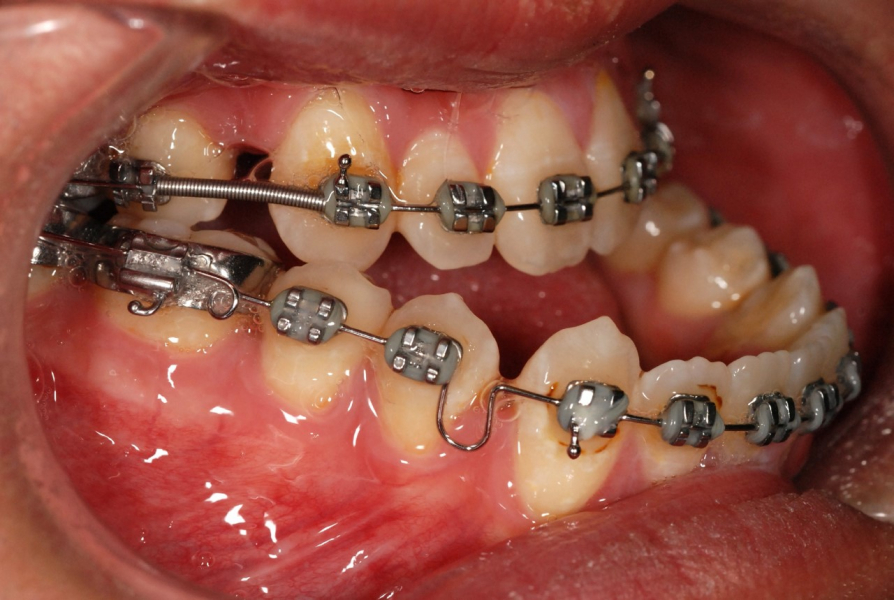

下顎前突症是一種面部畸形,在香港和南中國十分普遍,西方國家相對較少。矯正下顎前突症需要進行正顎手術,手術過程涉及切開顎骨並將它們固定在預先計劃的位置。口內垂直支骨切開術(IVRO)和矢狀支骨切開術(SSRO)是修復過長下顎的兩種常用手術技術。IVRO 是一種較傳統的技術,需要用鐵線固定上下顎 (俗稱鎖口),為期 6 周。在此期間,病人只能進食流質食物。相比之下,SSRO 會使用鈦金屬板和螺絲進行內部固定,手術後即可恢復顎骨功能。這兩項技術在香港和東亞地區都時常採用。

過去的研究指出,與 SSRO 相比,IVRO 對於下唇的感覺神經的損傷風險較低。而 SSRO 可能需要進行第二次小手術以移除外露或受感染的鈦金屬板和螺絲。然而,需要鎖口是一個問題,亦從未於病人的角度進行評估。